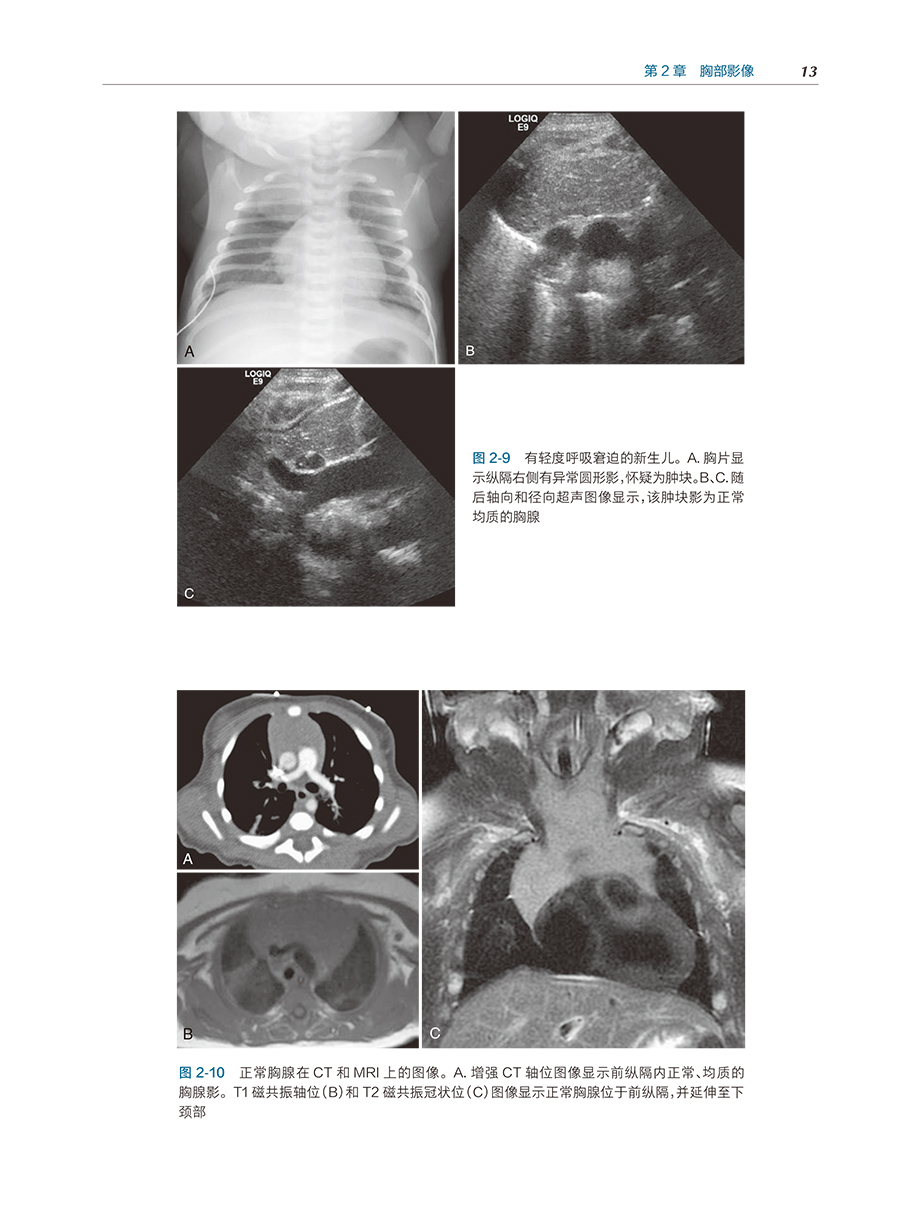

650余幅精美影像图片 根据发育阶段,注重生理解剖与病理状态对照 注重儿童影像与成人影像特征对比 体现了当前临床实例的最优成像选择 精选必备技术和核心技术